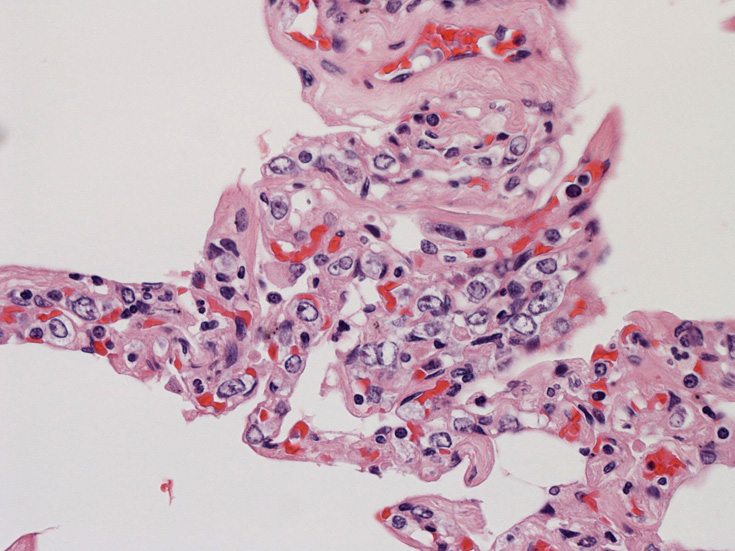

肺A;肺胞壁が厚くなり毛細血管内に腫瘍細胞が多数出現している(A).

肺組織所見